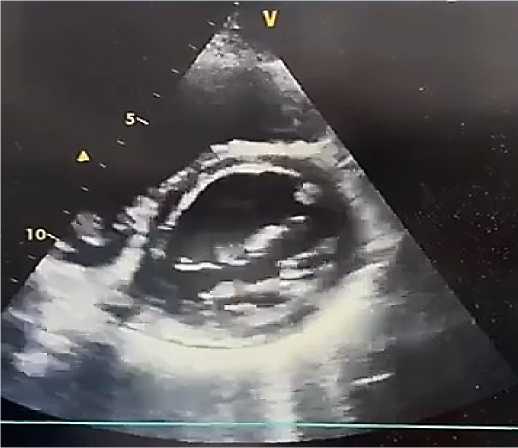

Эхокардиография. По данным ультразвукового исследования сердца у пациента А., 38 лет: толщина межжелудочковой перегородки — 0,9 см, задней стенки левого желудочка (ЛЖ) — 0,9 см. Фракция выброса ЛЖ (по Симпсону) — 38%. Размер левого предсердия — 4,5 см. Конечный систолический размер ЛЖ — 4,2 см, конечный диастолический размер ЛЖ — 6,1 см. Конечный систолический объём ЛЖ — 72 мл (референс: 18–68 мл), конечный диастолический объём ЛЖ — 168 мл (референс: 59–157 мл). Размер правого желудочка — 2,2 см, толщина его передней стенки — 0,4 см. Систолическое давление в лёгочной артерии — 32 мм рт. ст. Выявлены диффузный гипокинез миокарда ЛЖ, снижение систолической функции и нарушение процессов диастолического расслабления. Полости левых отделов сердца расширены. Перикард — без патологических изменений (Рисунок 2, 3, 4). Отмечены признаки атеросклеротического поражения аорты, аортального и митрального клапанов. Допплерографическое ультразвуковое исследование сонных и бедренных артерий: кровоток сохранён, признаков структурных и функциональных нарушений не выявлено. При обследовании венозных сосудов верхних и нижних конечностей тромбоз не диагностирован.

Рисунок 2. Эхокардиографическая картина миокардита у пациента А., 38 лет. Увеличение полости левого желудочка и митральная регургитация